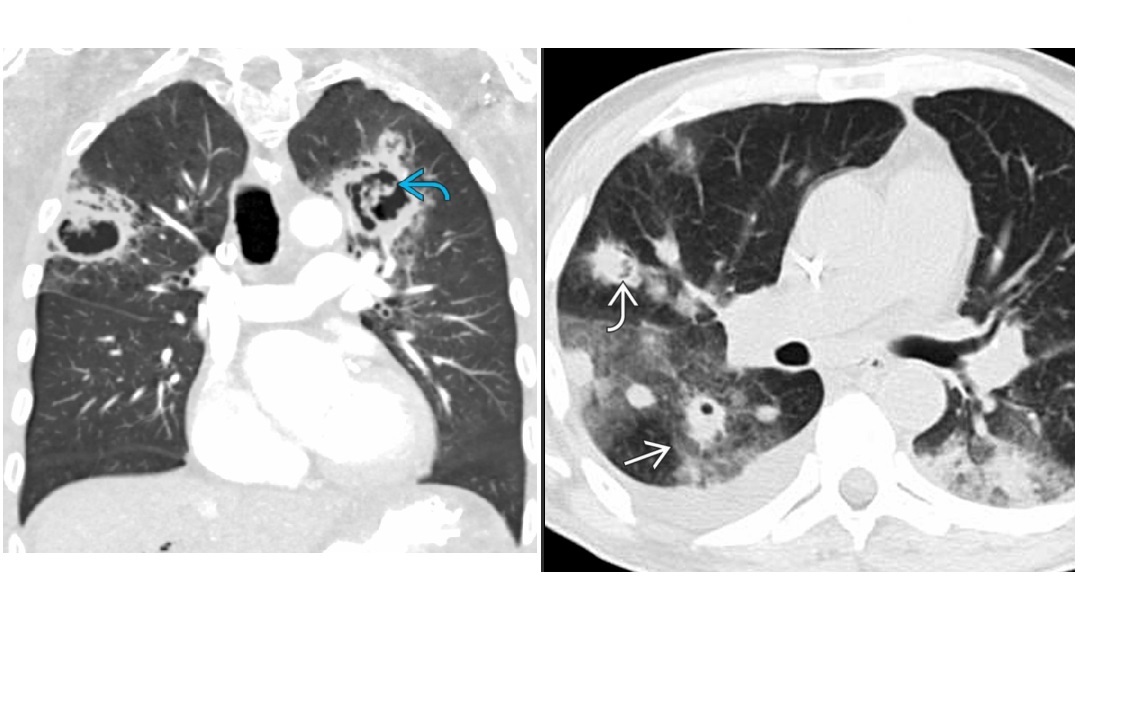

Angioinvasive aspergillosis

Halo sign

=Nodule/mass/consolidation surrounded by ground-glass opacity related to hemorrhage

Air crescent sign

=Crescent-shaped gas collection within nodule, mass, or consolidation

heralds improvement in the condition.